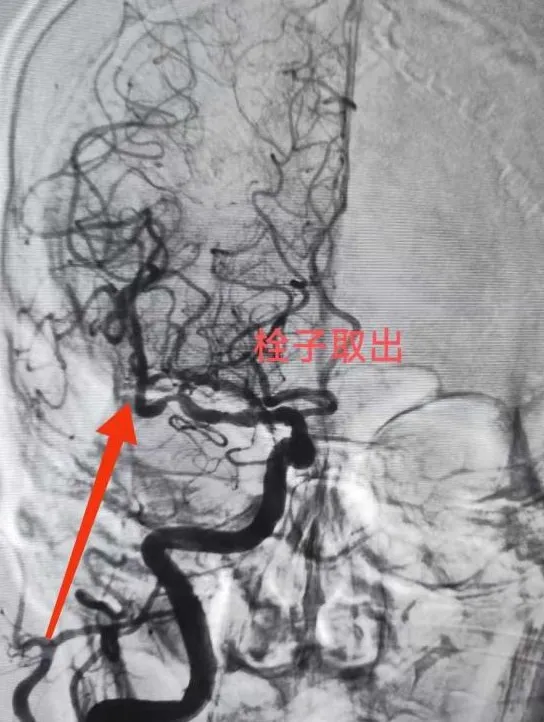

“必须立即进行脑动脉取栓手术!”神经内科王文杰主任了解患者详情后当机立断。与家属充分沟通并获得同意后,患者被迅速送入介入治疗室。术中造影显示,患者右侧大脑中动脉M1末端完全闭塞。术中造影发现患者多发动脉硬化、狭窄,血管迂曲明显,情况复杂,手术难度较高。且患者病情进展加重,王文杰、于弋水决定在局麻下为患者急诊动脉机械取栓。根据患者血管特点,选用合适导管行“血栓抽吸术”,仅一次操作即完整取出暗红色血栓,原闭塞血管血流瞬间恢复至最高分级(mTICI 3级),从穿刺到血管完全再通仅用50分钟。